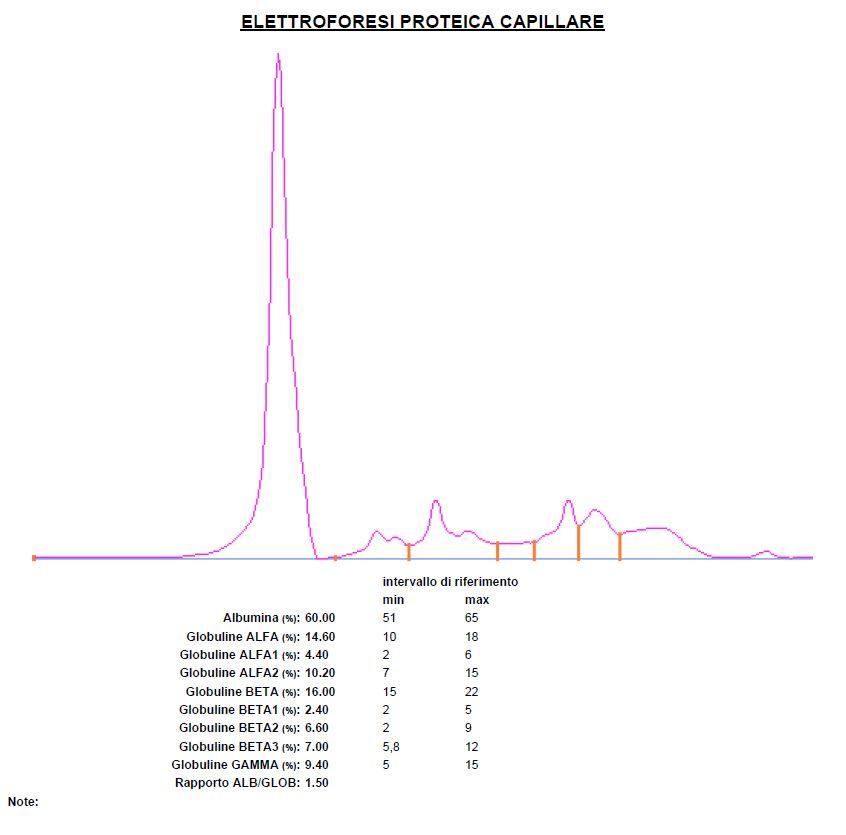

Vorrei chiedere, se possibile, il parere di un veterinario riguardo a degli esami del sangue fatti recentemente ad un cane di piccola taglia. Razza meticcia. Peso circa 9kg. Anni 9.

Chiedo qui perchè ho ricevuto gli esami per email, ma purtroppo è veramente difficile contattare i dottori telefonicamente, spero di passare presso l’istituto settimana prossima. Nel frattempo chiedo cortesemente consigli, dato che ci sono valori che forse non sono entro la norma.

Specifico che ho evidenziato io i valori che , secondo me, risultano sbagliati. Ovviamente non ho nessuna competenza in materia.